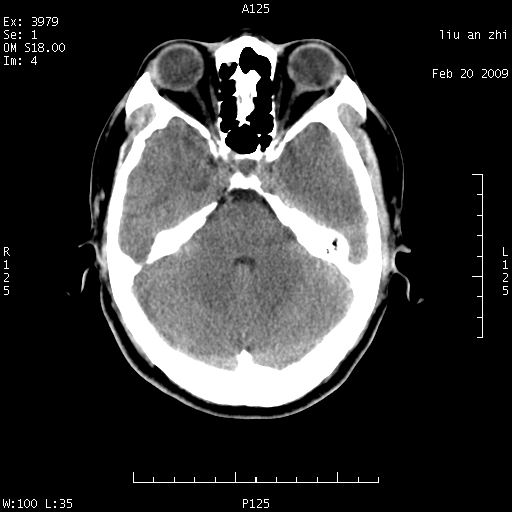

患者:男,32岁 被打伤后3天,自感头昏头痛作头颅ct检查。请大家看一下想什么??

7天后复查头颅ct片:

请注意小脑幕!!!

ct18448的结果:mri检查左侧天幕下血肿

以下是引用深蓝一号在2009-3-9 16:22:00的发言:[br]ct18448的结果:mri检查左侧天幕下血肿。